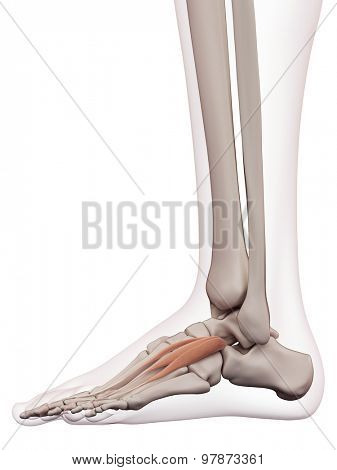

Extensor